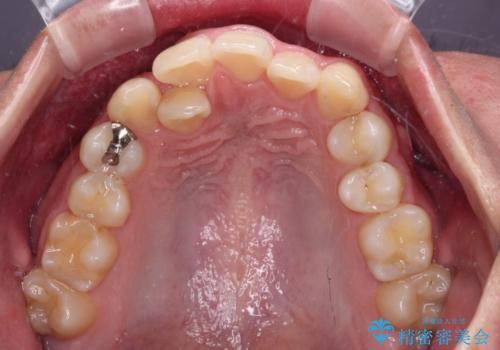

- 「前歯のデコボコが気になる」「前歯の中心がずれていて気になる」とご相談に来られた患者様の症例です。

診察の結果、上下の歯が並ぶためのスペースが不足しており、特に上顎右側の側切歯が内側(口蓋側)に転移していたため、正中が大きく右にずれている状態でした。

上下左右の第一小臼歯を抜歯してスペースを確保する計画を立てました。